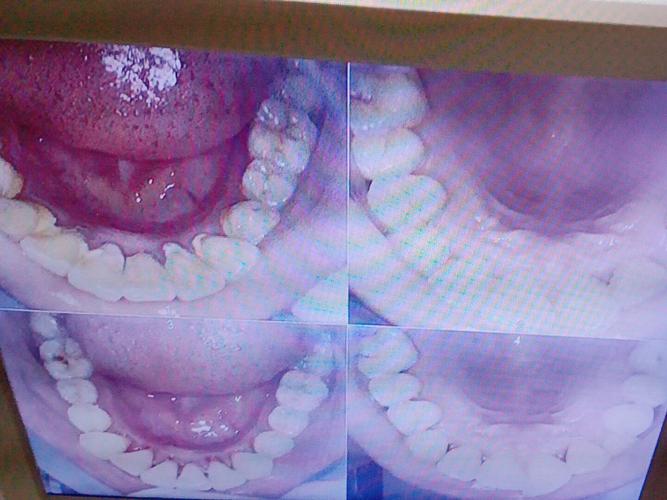

正畸治疗的核心是“诊断先行”,而科学的诊断离不开影像学检查,X光片如同医生的“透视眼”,能清晰显示牙齿、牙槽骨、颌骨、颞下颌关节等肉眼无法观察的结构,是制定个性化治疗方案、规避治疗风险的关键,部分患者反映,在正畸治疗中牙医并未安排拍片,这一现象背后可能隐藏着多种原因,但也可能带来潜在风险。

拍片是正畸诊断的“眼睛”,未拍片直接治疗如同“盲人摸象”,可能导致诊断偏差、方案错误,甚至引发严重并发症:

诊断遗漏:关键信息“隐形”

- 牙齿与牙根问题:X光片可发现埋伏牙(如上颌尖牙埋伏)、多生牙、牙根弯曲/吸收、牙根形态异常(如锥形根)等,未拍片可能忽略这些问题,导致治疗中意外损伤牙根、邻牙,或埋伏牙压迫牙根造成吸收。

- 牙槽骨与颌骨状况:全景片和头颅侧位片能显示牙槽骨高度、厚度,以及颌骨发育情况(如下颌前突、上颌后缩的骨性因素),若未评估骨量,可能错误选择非拔牙方案(如通过扩弓解决拥挤,实际骨量不足导致牙根暴露、骨开裂),或本该拔牙却选择掩饰性治疗,效果不稳定。

- 颞下颌关节(TMJ)问题:部分患者存在关节弹响、疼痛、张口受限等症状,需通过关节片或CBCT排查关节结构异常(如关节盘移位、骨关节病),未拍片直接矫正可能加重关节负担,引发不可逆的关节损伤。